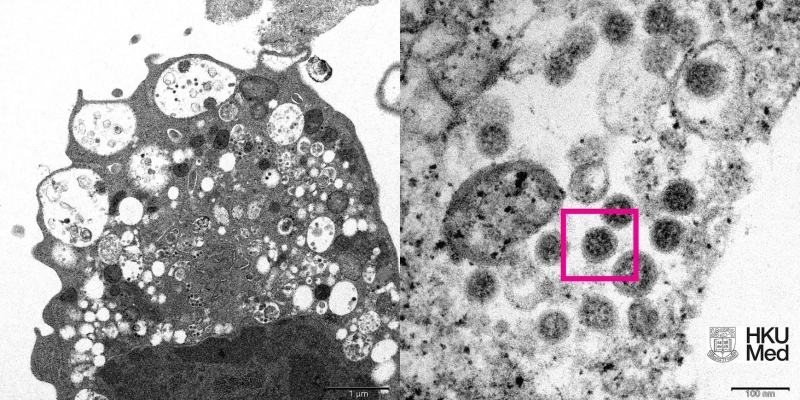

香港大學醫學院近日研究發現,新型冠狀病毒變異株Omicron相較Delta及原始病毒株,在人類支氣管組織複製得更快。負責研究的公共衞生學院副教授陳志偉今日(16日)在電台節目指,於感染24小時後,Omicron的病毒量比Delta多近70倍,估計比原始病毒株更高近100倍,病毒量越大,傳播力就越高。

(資料圖片) 陳志偉認爲短期内Omicron在全球會取代Delta,成爲主流病毒株,而接種新冠疫苗加强劑有助應付Omicron病毒,呼籲市民盡快打第三針,以防止社區出現爆發。 陳志偉指,研究又發現Omicron於肺部組織的感染就遠比原始病毒株為低,但不代表Omicron帶來的威脅較少,不少重症病人並非只出現肺部感染,亦會有不正常的免疫反應,認爲Omicron有機會引致更多重症及死亡。 【編輯:张琦】